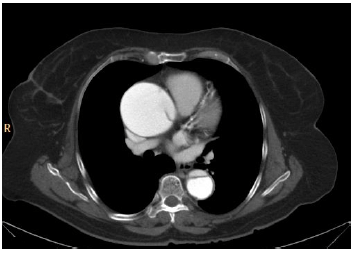

Analise a imagem a seguir.

A análise da imagem de tomografia computadorizada acima sugere que